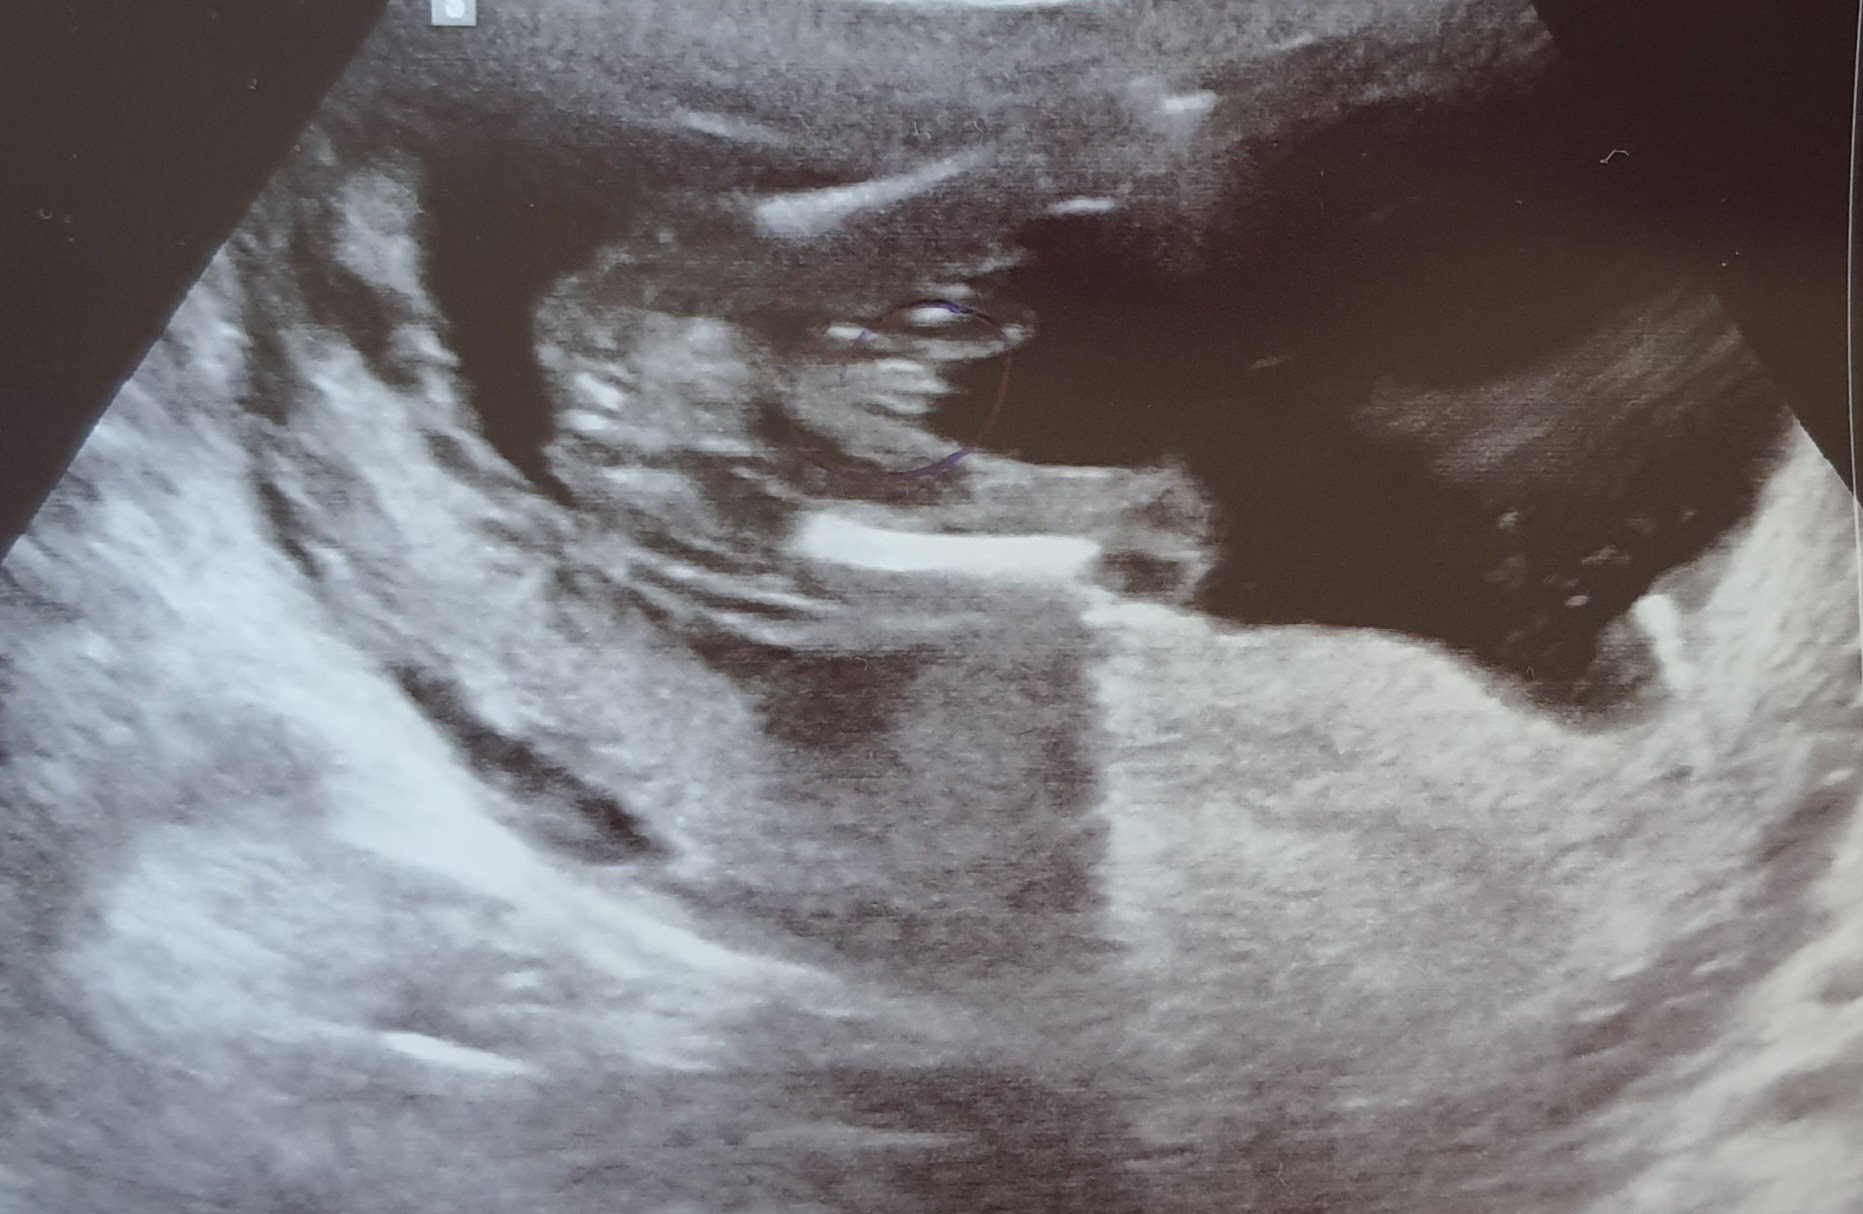

Ja bym z tym określaniem płci uważała, mi lekarz na prenatalnych w 12. tygodniu mówił ze chłopak a wczoraj byłam na połówkowych i mówi, ze dziewczynka 😅

Na pierwszych często nie są pewni niestety, mnie nawet nie chciał powiedzieć płci, dowiedziałam się dopiero w 18tc.

Tylko wiesz, jeśli lekarz nie miał 100% pewności, to dziewczyny które nie są specjalistkami tym bardziej nie będą wiedziały na pewno.

Słyszałam, że jednak częściej mylą się mówiąc że będzie dziewczynka, a później okazuje się że jednak chłopczyk. Więc w drugą stronę. Ale to właśnie "słyszałam" i też nie ma reguły.